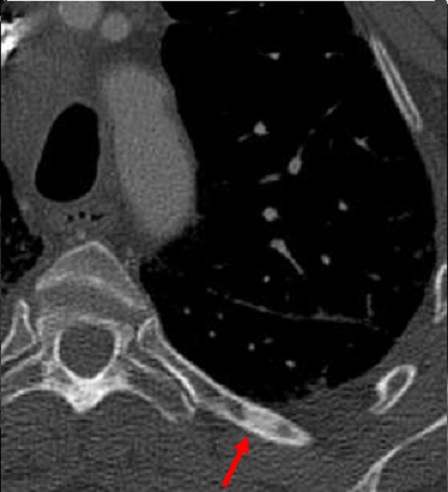

Image radiologique TDM d'une

tumeur metastatique secondaire de type condensant (

fleche rouge ) de l'arch posterieure du côte

thoracique gauche |